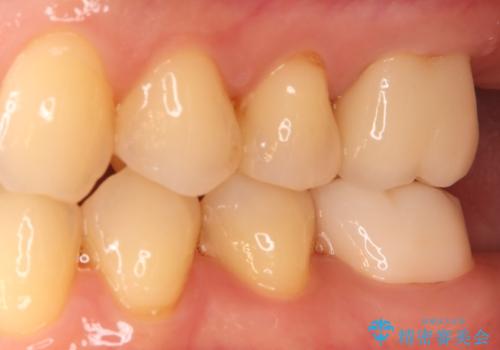

根の状態が安定した後、金属を一切使用しないオールセラミッククラウンを装着しました。高い適合精度により二次感染のリスクを抑え、天然歯に近い透明感と耐久性を両立させています。根の違和感も解消され、機能・審美ともに健康な状態を取り戻しました。